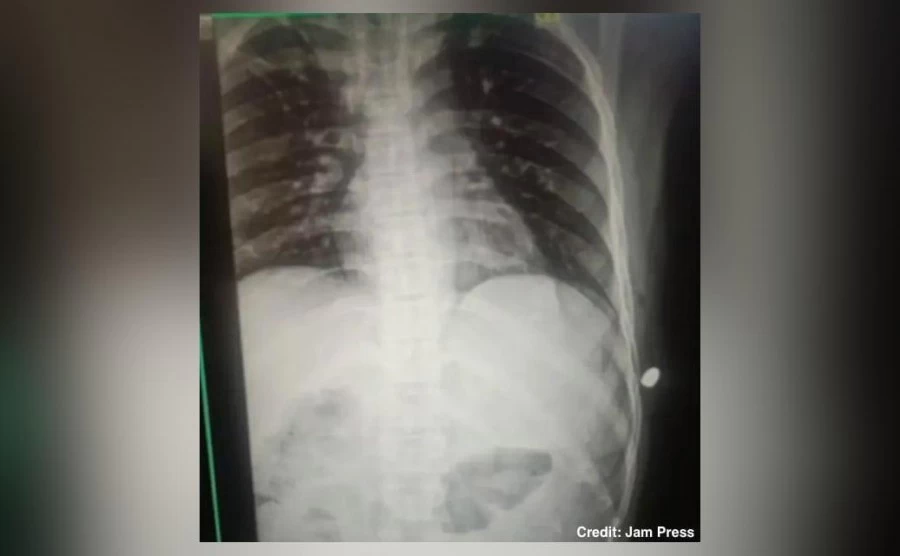

An x-ray revealed the bulled was lodged under his skin and missed his vital organs by a few centimeters. Soon after the scans, Chand underwent surgery to have the bullet removed on September 17.